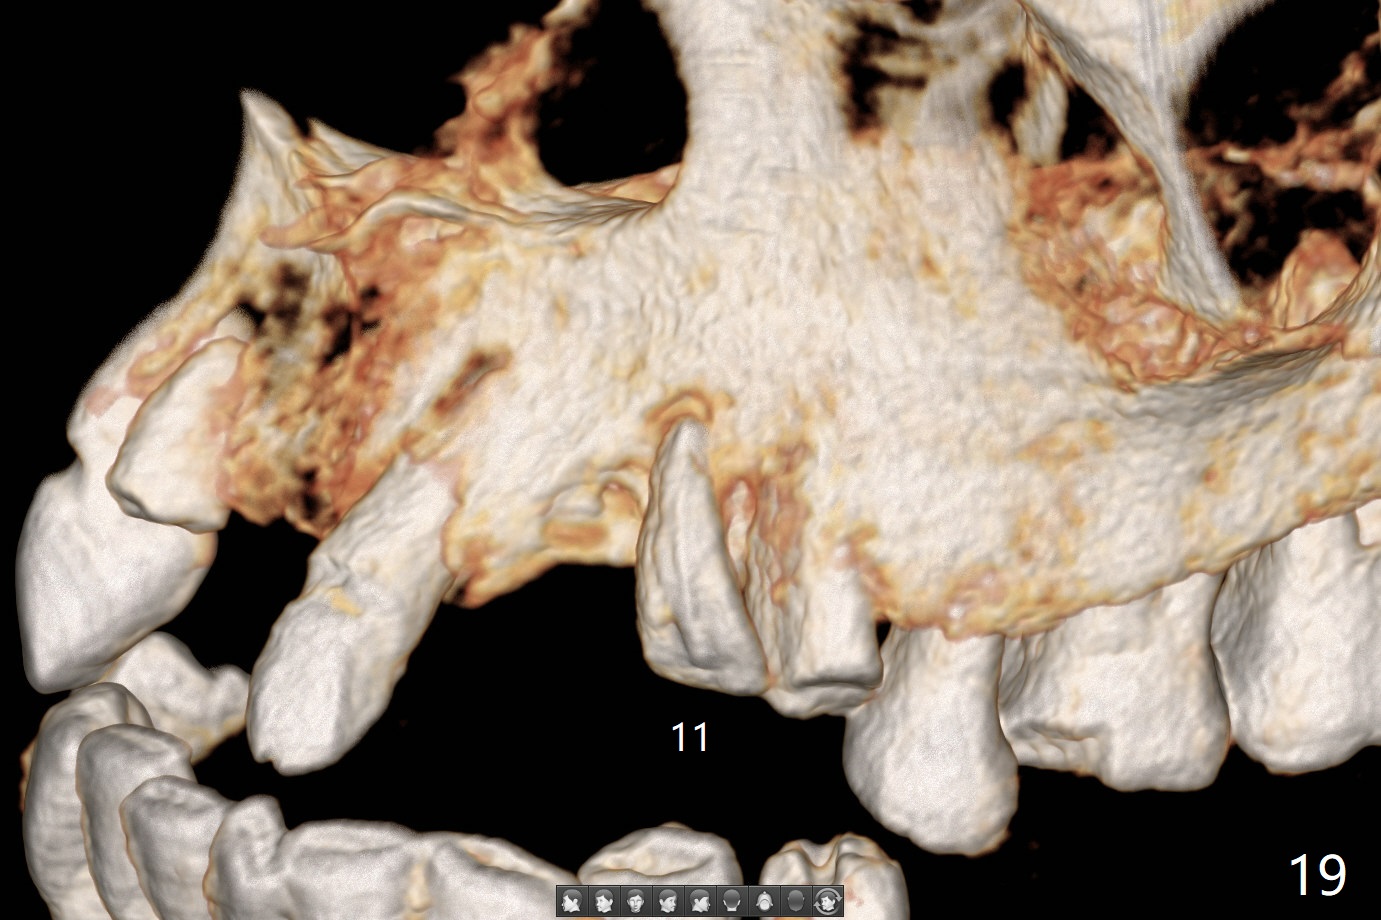

今天下午进入治疗室,粘性骨粉已制备:上清液来自红管(含促凝剂),离心3分钟(图一);再离心10分钟上清液就转变PRF,压制后,使用前剪成三块(图二:黑线),其中两块punch一个洞(图二:圆圈),插入7,9号牙基台固定;大块覆盖11/12号牙牙槽窝(图十四)。7,9,11,12号牙必须拔除(图三),然后在7,9,12种植。由于缺失左下磨牙,前牙垂直距离减少(图四)。完成9号牙位钻洞后,利用fixture mount(图五:M)植入植体,并留在原位固定导板(图六),然后7号牙种植,也留下fixture mount(图六:7,9),最后完成12号牙植入,但是后者扭力低,放置愈合螺帽(图九),而7,9号牙位放置修复基台(图七,八(使用5.5毫米profile drill后),好像基台没有完全就位。7号牙位更换基台似乎没帮助(图十),9号牙位再次放置同一个基台临床上仿佛有改变(比较图八与十二)。放置粘性骨粉后(图十一至十三),牙槽窝口覆盖PRF膜(图十四:P(A:基台)),最后使用树脂敷料固定骨粉和膜(图十五,六),基台帮助敷料固位,没有咬合干扰(图十七:*)。树脂敷料部分解决美观问题,一个月后撤除,如果植体仍有稳定性,可能制作7-10临时牙桥,可能部分维持或者恢复牙龈外形。术后一周病人主诉后面植牙和鼻底疼痛,11号牙根尖牙龈充血(图十八),轻度触痛,可能与术中尚未完全清创有关(图十九(术前CT 3D图像))。再服用Amoxicillin一周,症状好转,鼻底轻度触痛(图二十)。术后1.5月没有任何不适,撤除树脂敷料,7号牙基台(袖)显得太长,换一个短的(4.5x4(5)(图十,十一)->4x4(3)毫米)毫米),植骨好像愈合正常(图二十一:*)。7号牙换了短的基台,9号牙基台高度调整后,与对合牙有足够空间做临时牙桥,最好8,10号牙位牙龈应该凹陷(图二十二:*),有pontic外形。另外9号牙基台颊侧牙龈边缘有所修整,临时牙桥准备。先做7-10临时牙桥,理想临时牙桥pontic处树脂应该多些(图二十三:白线)压迫牙龈形成凹陷。11,12号牙牙槽窝在树脂(Bosworth)敷料下也正常愈合(图二十四)。